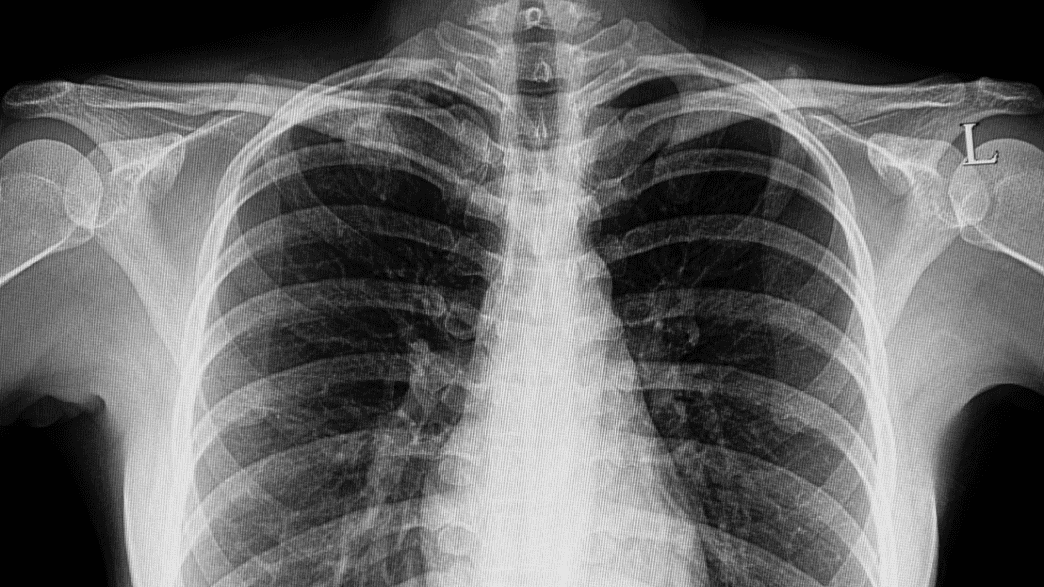

Dark lung fields Peanuts In Lungs aspiration pneumonia is a lung infection in which the lung gets inflamed and filled with fluid. when you aspirate, food, drink, or small objects you've inhaled go into the airway or lungs instead of your stomach. It happens when tiny air sacs within the lung,. nut and other small organic foreign bodies account for a significant portion. Peanuts In Lungs.